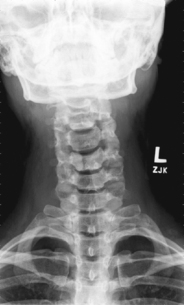

AP (PA) dens (Fuchs and Judd methods) (S)

AP open mouth and AP (PA) dens critique